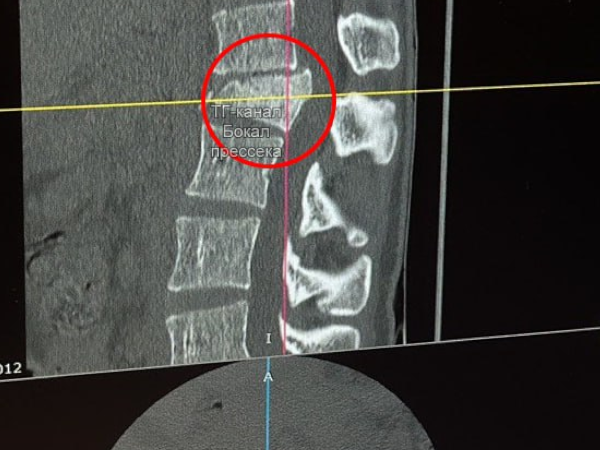

Несмотря на приземление на асфальт, нижегородец сломал только первый поясничный позвонок. Его доставили в Нижегородскую областную больницу имени Семашко, где успешно прооперировали.

Для этого нейрохирург Артем Копылов распечатал на 3D-принтере макет поврежденного участка, на котором врачи поупражнялись перед проведением настоящего вмешательства.

После этого они выполнили транспедикулярную фиксацию позвоночника.